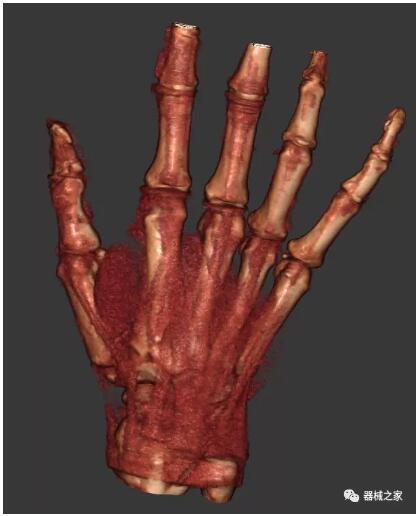

另外一款被稱為世界上最小的CT,它的重量僅300磅,不僅能夠掃查足部,還可以檢查膝蓋和上肢等。

以上介紹的CT均來自國外同一家公司,這些CT均配置了可視化軟件,可以進行切片、3D重建以及大型CT附帶的所有典型的操作功能。

以下是這些“特立獨行”的CT所拍出來的圖像: